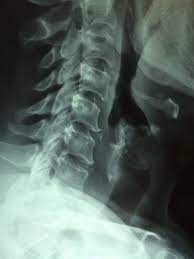

- X-레이 (X-ray): X-레이는 척추의 구조를 보는 데 사용됩니다. 디스크의 이상이나 척추 골절 등을 확인하는 데 도움을 줄 수 있지만, 디스크 자체의 세부 정보는 제공하지 않습니다.